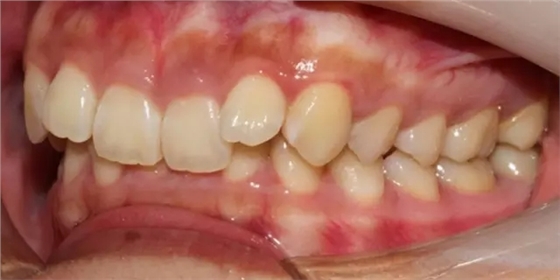

上下牙列擁擠,磨牙尖牙Ⅱ 類關(guān)系,3 度的深覆牙合,上頜中切牙伸長內(nèi)傾拔除上頜雙側(cè)的第一前磨牙,先粘上頜高轉(zhuǎn)矩的自鎖托槽排齊牙列,唇向開展上頜切牙,有一定的覆蓋,粘下頜標準轉(zhuǎn)矩托槽,上頜 1, 2 之間植入種植支抗壓入,同時后牙 5, 6 之間植入種植支抗內(nèi)收前牙,打開咬合關(guān)閉間隙。治療關(guān)鍵:前牙轉(zhuǎn)矩的控制第 1 個月 上頜粘上 Damon Q 高轉(zhuǎn)矩托槽,上 .014 熱激活 NiTi 絲。第 3 個月 上換 .014 x .025 熱激活 NiTi 絲。第 5 個月 上頜基本排齊,覆蓋增大,上換 .017 x .025 NiTi絲,下頜粘托槽,下 .014 熱激活 NiTi 絲。第 7 個月 上 .017 x .025 NiTi 絲加搖椅,下?lián)Q .014 x .025 熱激活 NiTi 絲第 9 個月 上頜換 .019 x .025 NiTi 絲加搖椅,下頜換 .017 x .025 NiTi 絲第 11 個月 下頜換 .019 x .025 加搖椅,上頜 1, 2 之間, 5, 6 之間植入種植釘,下頜出現(xiàn)散隙。第 13 個月 上頜換 .019 x .025ss 加搖椅,前牙種植釘用 Power Chain 壓低前牙(每側(cè) 100g),后牙種植釘關(guān)閉間隙(每側(cè) 150g),下?lián)Q .019 x .025ss,Power Chain 關(guān)閉間隙。第 19 個月 上頜前牙基本壓低到位去除前牙種植釘,繼續(xù)用關(guān)閉間隙,下頜散隙關(guān)閉。

第 22 個月 上頜覆蓋變小,去除 5, 6 之間種植釘,后牙前移關(guān)閉間隙。第 30 個月 患者未配合中線牽引,下中線仍有 1mm 右偏,患者對矯治效果滿意要求拆除,拆除固定矯治器,取模制作壓模保持器。 1.骨性 Ⅱ 類的患者內(nèi)收前牙時需對上頜前牙的轉(zhuǎn)矩進行較好的控制才能獲得良好的面型和唇部形態(tài)。 2.露齦笑的患者治療前要分析其病因是唇、牙齦、牙齒、牙槽骨、上頜骨或多種因素結(jié)合,再制定矯治方案。 3.Ⅱ 類第二分類伴露齦笑的患者的上頜前牙移動軌跡是唇向開展-壓低-整體內(nèi)收。 4.Ⅱ 類第二分類牙齒舌傾比較厲害的情況,上頜中切牙慎用樹脂咬合墊。 5.壓低前牙或控根移動時容易發(fā)生牙根的吸收,需輕力緩慢的移動。